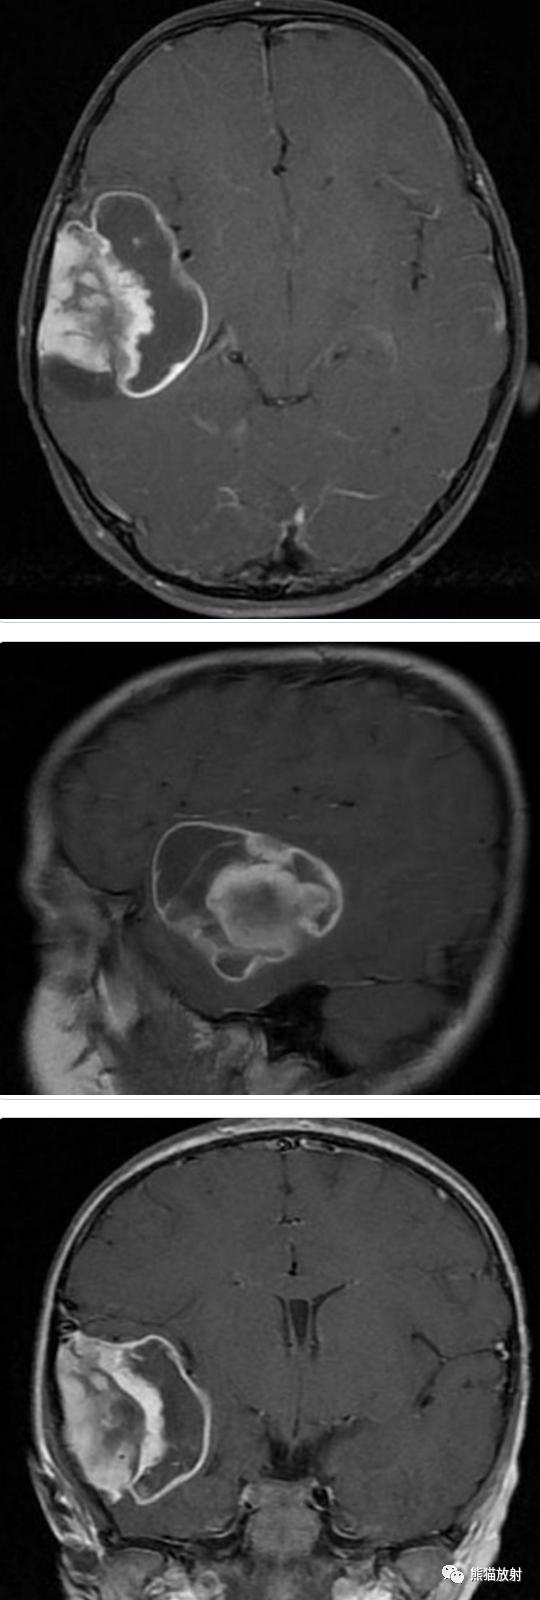

男性,14岁,癫痫发作数月。

⭐️ 多形性黄色星形细胞瘤

Pleomorphic xanthoastrocytoma

青少年 癫痫 颞叶 囊实性占位 病灶表浅 累及脑膜 实性部分位于脑表面 明显强化